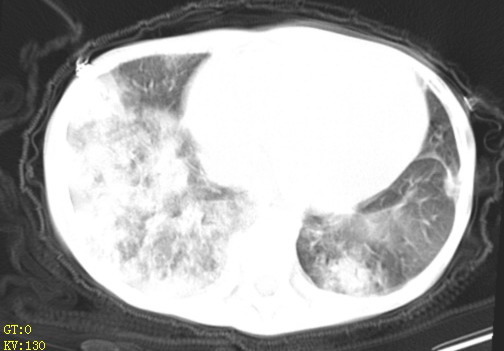

女,12岁,气促、咳嗽2天,3个月前查胸片示:两肺感染,急诊入院查ct,血常规等未检查。

双肺中下野不规则片絮状阴影,中外带明显,双侧胸腔少量积液,心影增大,心腔密度减低,隆突下及左侧气管旁见钙化淋巴结影,考虑双肺感染、心衰;建议结合临床除外h1n1并急性心衰,先心不能排除。

两肺多发片絮状模糊影,以下肺外带居多,内见支气管气像,纵膈窗未减影,两侧胸腔积液,心影增大,结合心超,支持重症肺炎,非常时期,甲型h1n1流感不排除。

1、左心房、左心室增大,考虑左心衰, 2、肺水肿合并感染 3、双侧胸腔积液